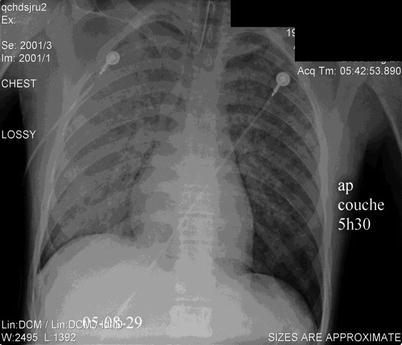

This unopposed sympathetic stimulation mediates the myocardial injury and is also likely responsible for the neurogenic pulmonary edema often seen in the management of patients with acute elevations of ICP (Fig. 38.2) [38]. Practitioners should be aware of this fulminant presentation of sudden onset respiratory failure with large volume, frothy tracheal secretions. In primate models of acute intracranial hypertension, acute heart failure ensues with reversal of flow in the pulmonary circulation due to massive rises in left atrial pressure [33]. Rupture of pulmonary capillaries can occur from this retrograde increase in vascular hydrostatic pressure [39]. This hydrostatic pulmonary edema is responsive to high PEEP and is generally reversible with time [40, 41].

Fig. 38.2.

Chest x-ray showing neurogenic pulmonary edema in an adolescent with acute intracranial hypertension